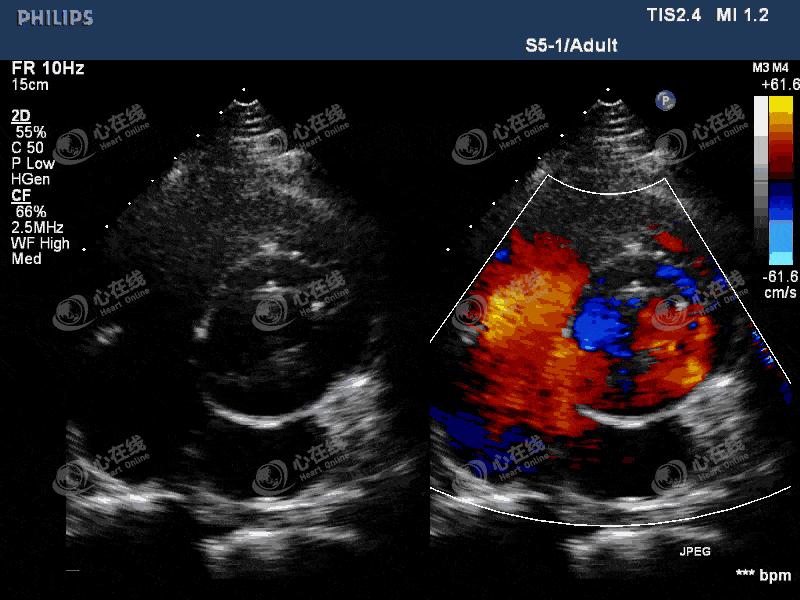

图2 左室长轴切面:彩色多普勒示,机械瓣瓣环外侧可见中量血流信号进入左室,另可见机械瓣中心性反流信号。主动脉根部膜样回声破口处可见血流信号,来自主动脉,并穿梭于该无回声区内。

图3 四腔心切面:彩色多普勒显示中量偏心性反流信号,起自主动脉瓣机械瓣环外侧。